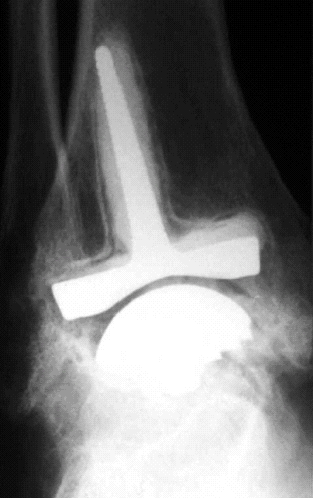

Buechel-Pappas Total Ankle8,9 (Fig. 12)

Fig. 12: Anterior A and lateral B, views of Buechel-Pappas total ankle

prosthesis.

a.. The mobile bearing reduces excessive stress transfer to the

bone-prosthesis interface.

b.. There is full conformity between the polyethylene component and the

tibial and talar components.

c.. The prosthesis resurfaces only the tibiotalar area and not the facets.

d.. Because the bearing is mobile, there is automatically backside wear.

e.. The tibial component has a short stem. This may potentially protect

tibial trabecular bone but avoid the excessive stress shielding from an

overly long stem.

f.. The talar component is an on-lay component with two fins for fixation.

It preserves most of the talar dome. Since it does not resurface the medial

and lateral talar facets it thereby helps preserve talar cortical bone.

g.. The flat upper surface of the mobile bearing may reduce

anteroposterior stability.

Star30, 31 (Fig. 13)